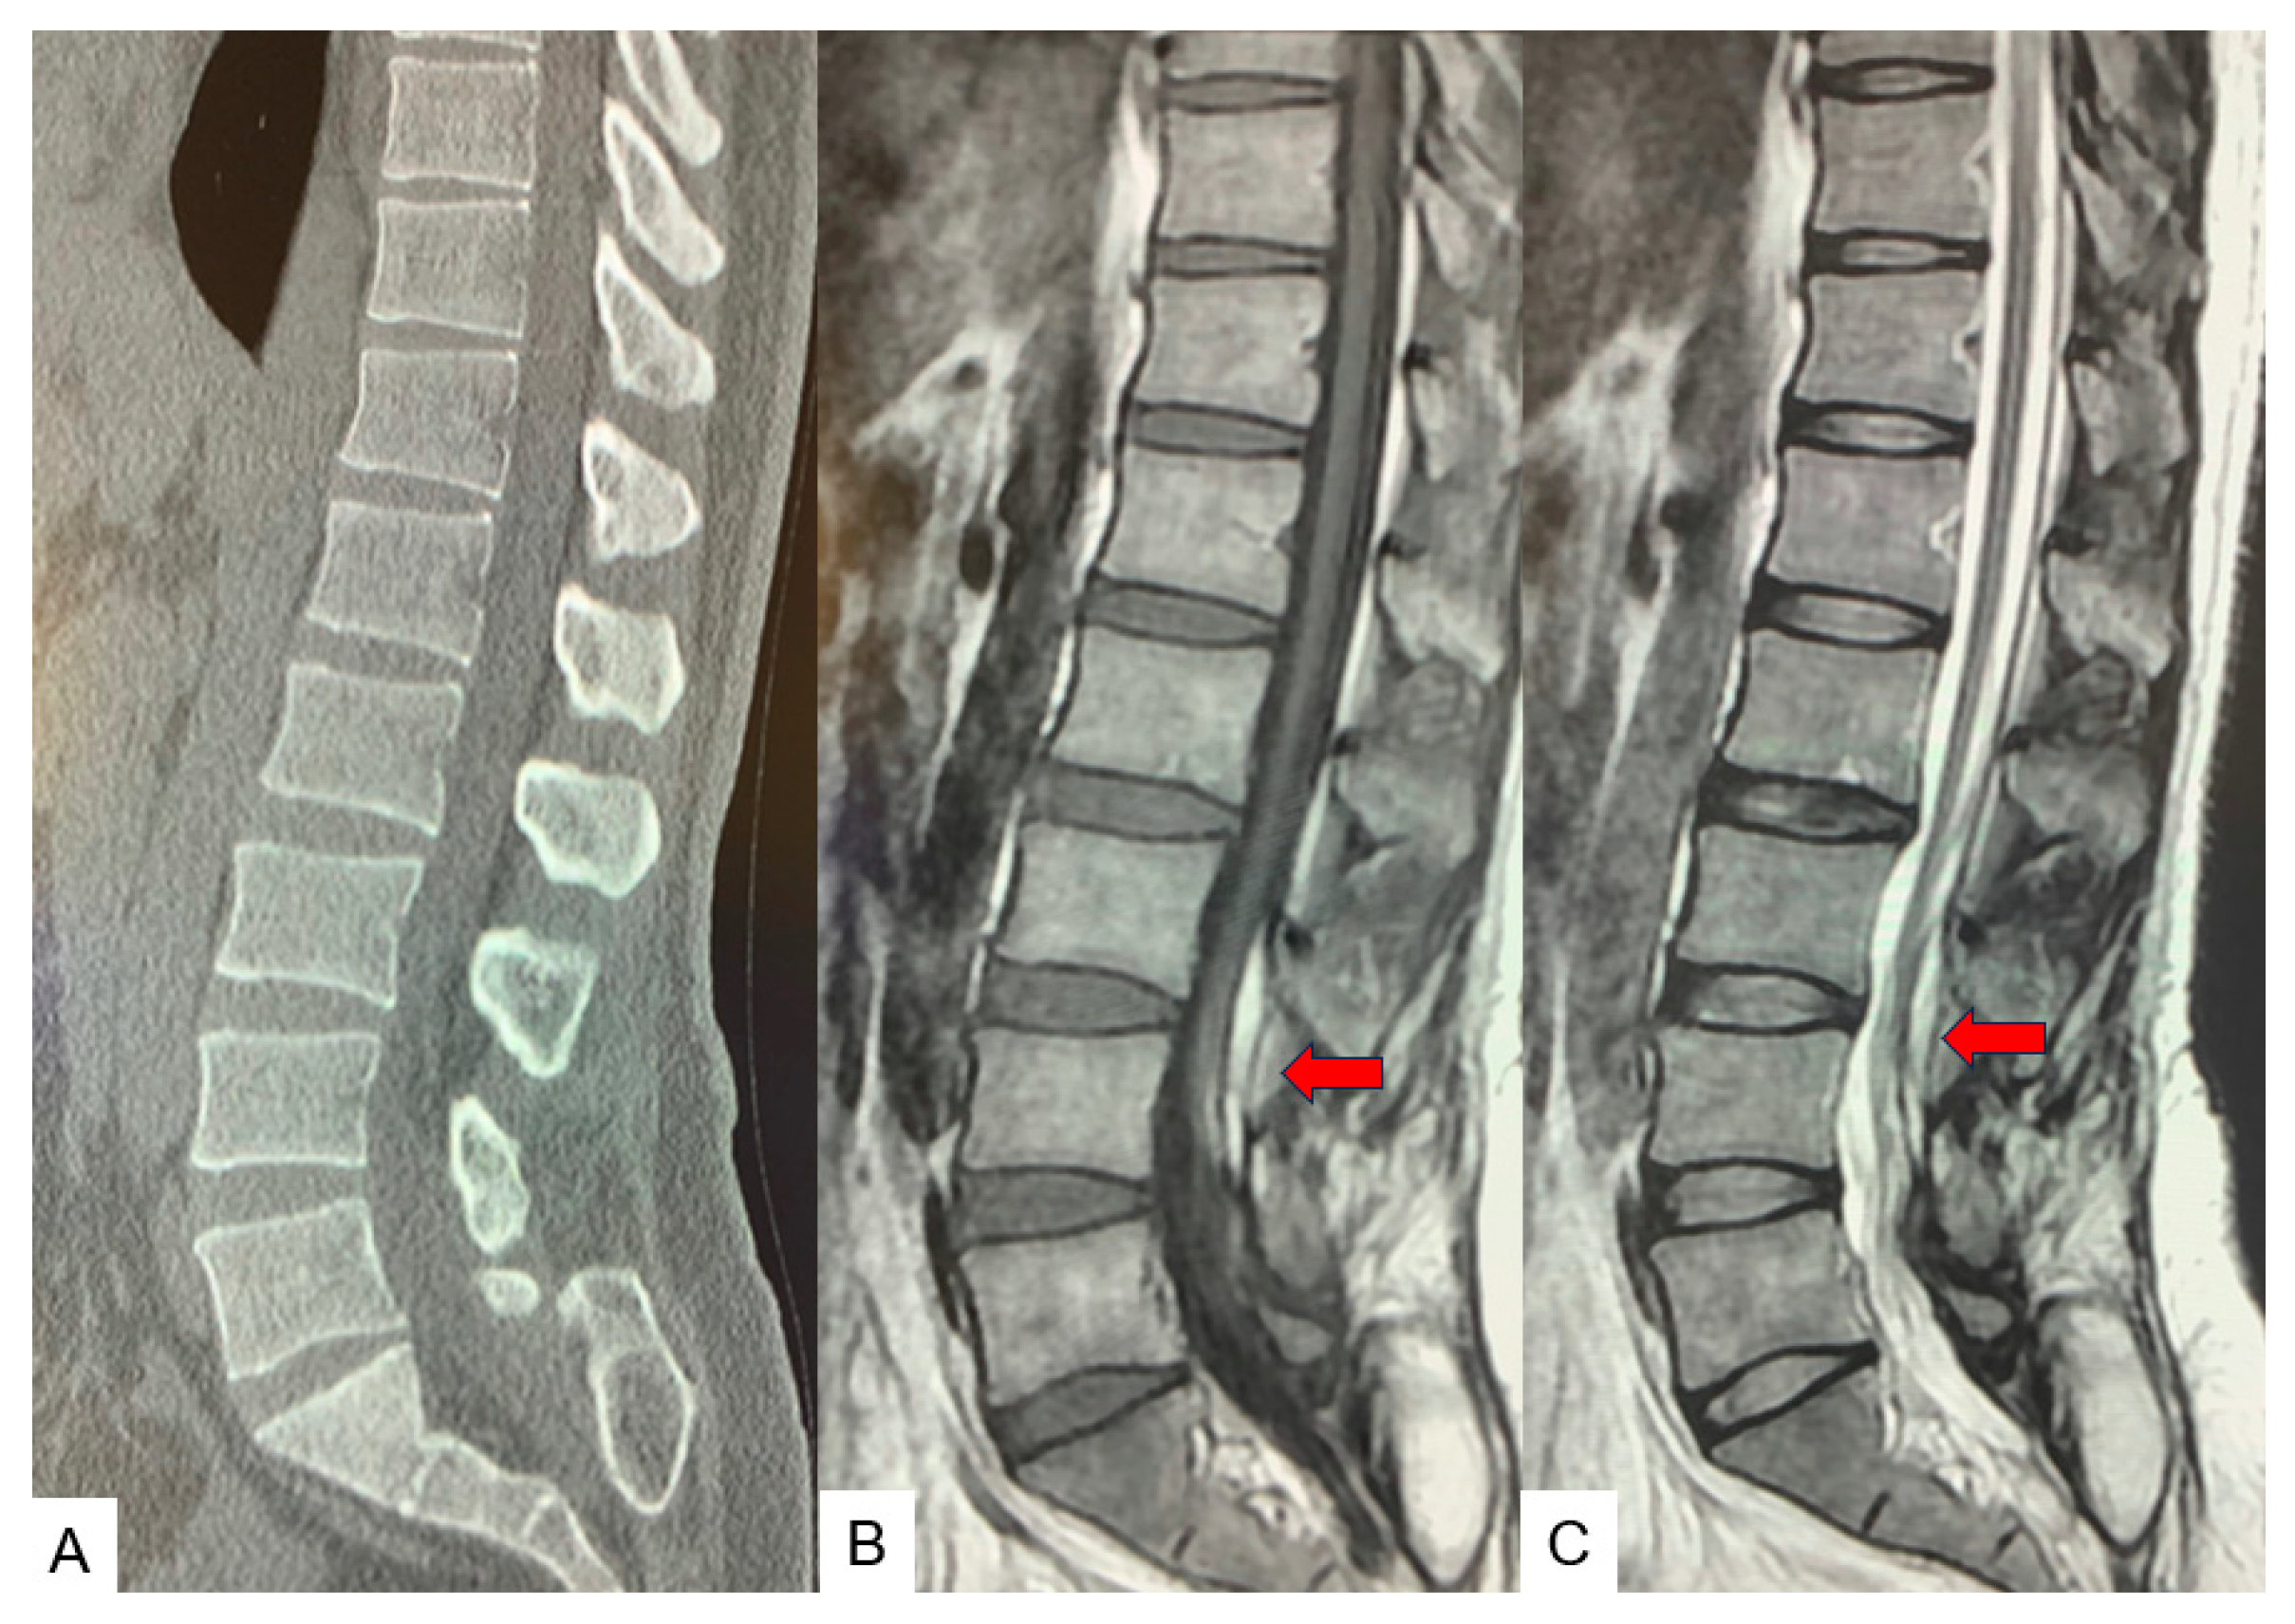

2.3. Preoperative Imaging

3. Case 2: 33-Year-Old Male, Tethered Cord Syndrome, Conventional Technique